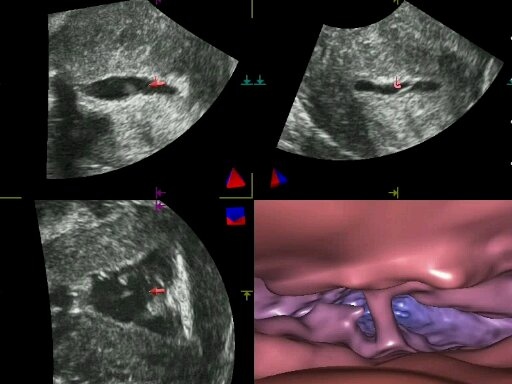

Estas técnicas, desarrolladas por el equipo formado por el doctor Tesarik y la doctora Raquel Mendoza-Tesarik, de la Clínica MARGen, y el doctor Nicolás Mendoza, de la Universidad de Granada, ofrecen imágenes en 3D de las cavidades y canales de diferentes órganos reproductivos femeninos, sin necesidad de penetrar físicamente en su interior, creadas a partir de una reconstrucción computarizada de grabaciones ecográficas realizadas desde el exterior.